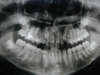

Les radios après le traitement